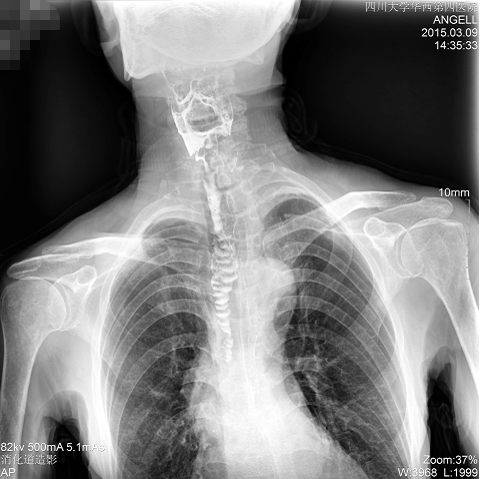

如下圖所示:該患者因吞咽時感到很難受,進食時也經(jīng)??人怨示歪t(yī)診斷。華西醫(yī)院醫(yī)生使用動態(tài)DR為病人進行消化道造影診斷,要求他吞鋇后發(fā)現(xiàn),食道各段通過順利,形態(tài)規(guī)則,雙側(cè)梨狀窩不對稱左側(cè)稍淺,多次吞咽動作后,仍見鋇劑滯留,并見鋇劑進入氣管,屬于會厭征陽性。會厭功能紊亂,鋇劑進入了氣管。

圖為正位:通過動態(tài)影像可以清楚看到鋇劑進入了支氣管道且雙側(cè)梨狀窩不對稱